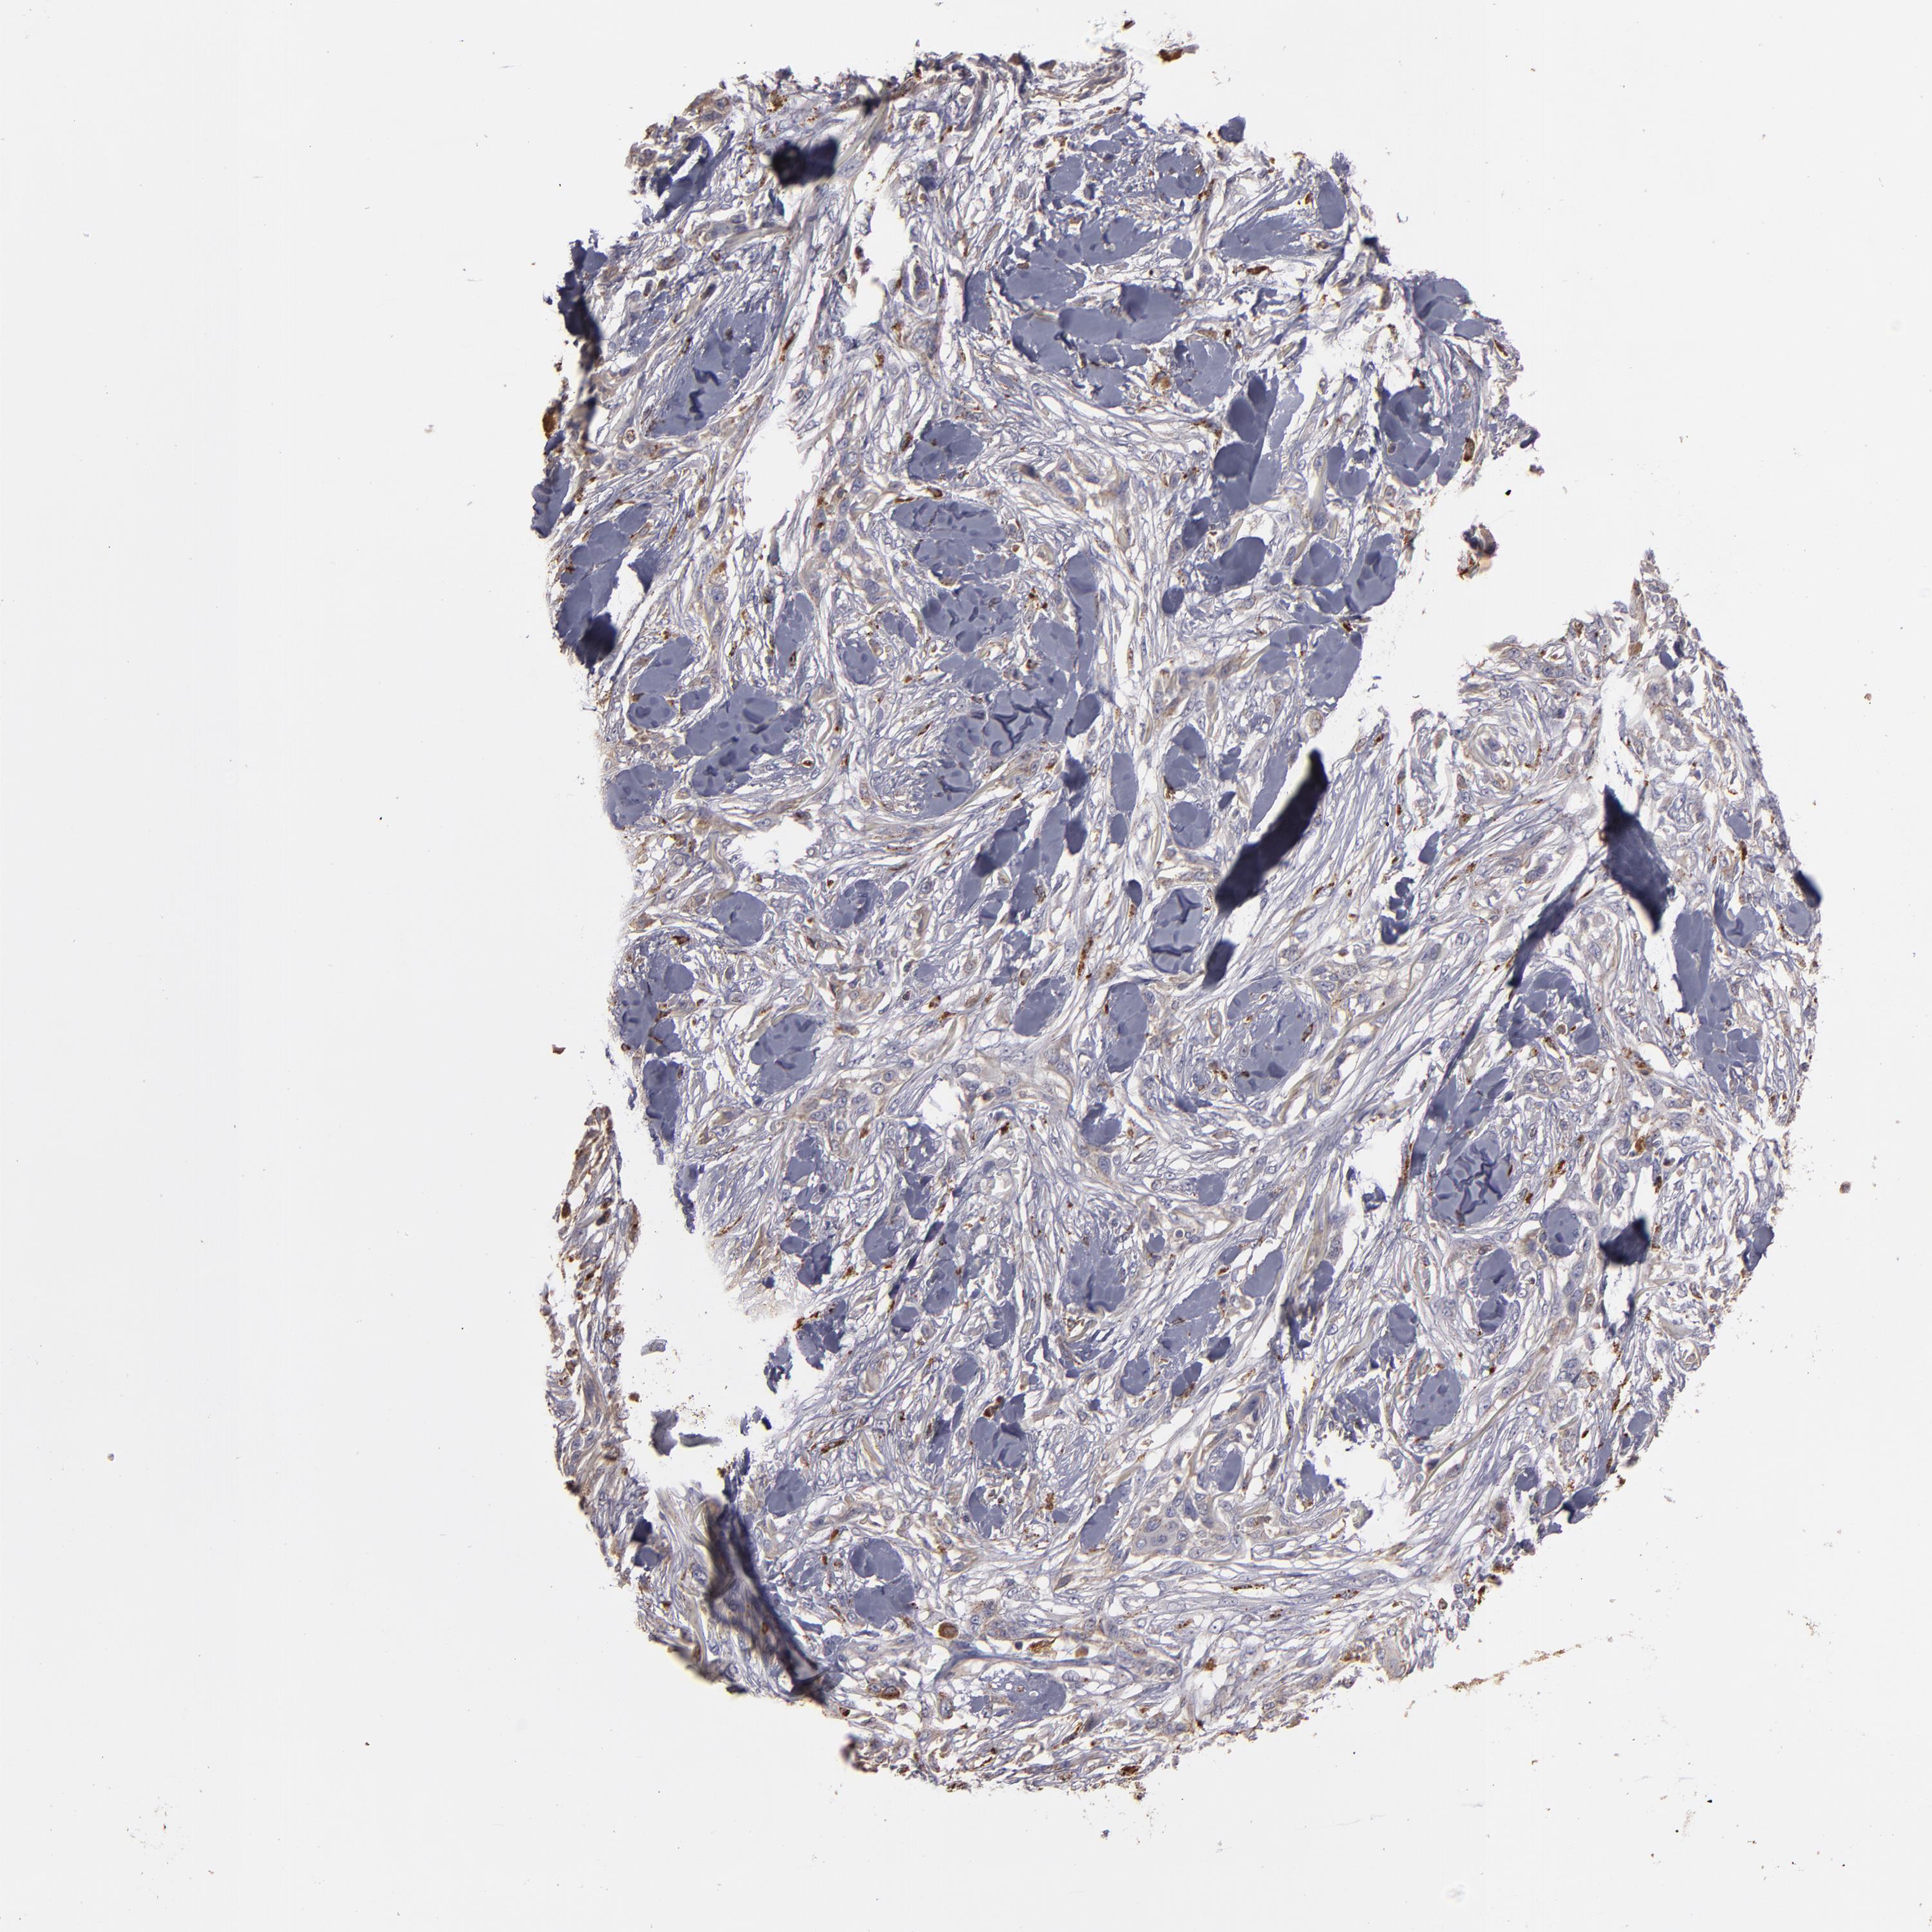

SKIN CANCER - Protein expressioni

A mouse-over function shows sample information and annotation data. Click on an image to view it in a full screen mode. Samples can be filtered based on level of antibody staining by selecting one or several of the following categories: high, medium, low and not detected. The assay and annotation is described here.

Each image is clickable and will lead to virtual microscopy that enables deeper exploration of all samples and also displays staining intensity scores, fraction scores and subcellular localization as well as patient and tissue information for each sample.

Antibody HPA001852

Antibody CAB009593

Squamous cell carcinoma, NOS

Basal cell carcinoma